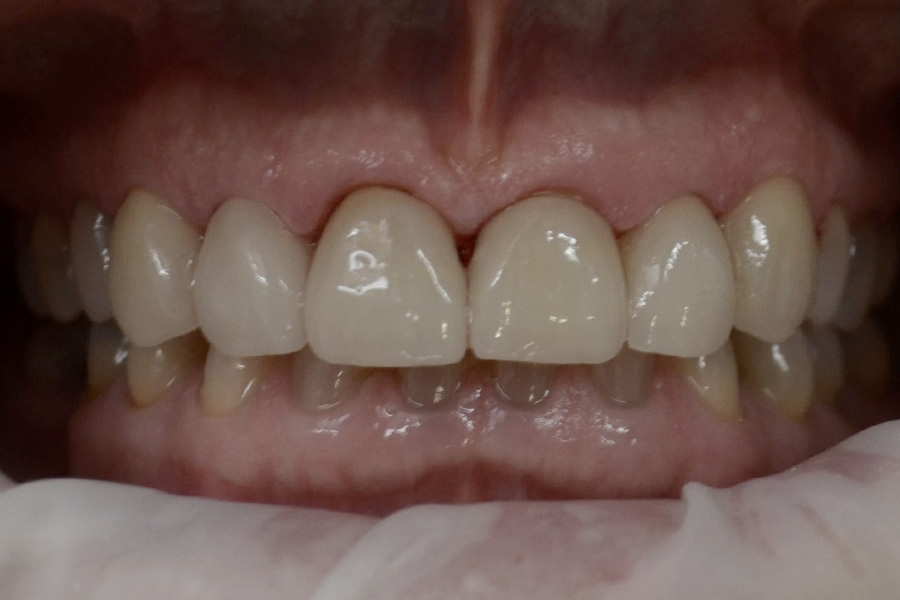

Brooke had a single crown on the upper left central incisor that had a receding gum line.

Some of the white fillings on other front teeth were also stained. Deb decided to have the crown replaced and ceramic veneers placed on other teeth. The new crown on the upper left central incisor is all ceramic (without any metal on the inside) and blends in more naturally with the veneers.